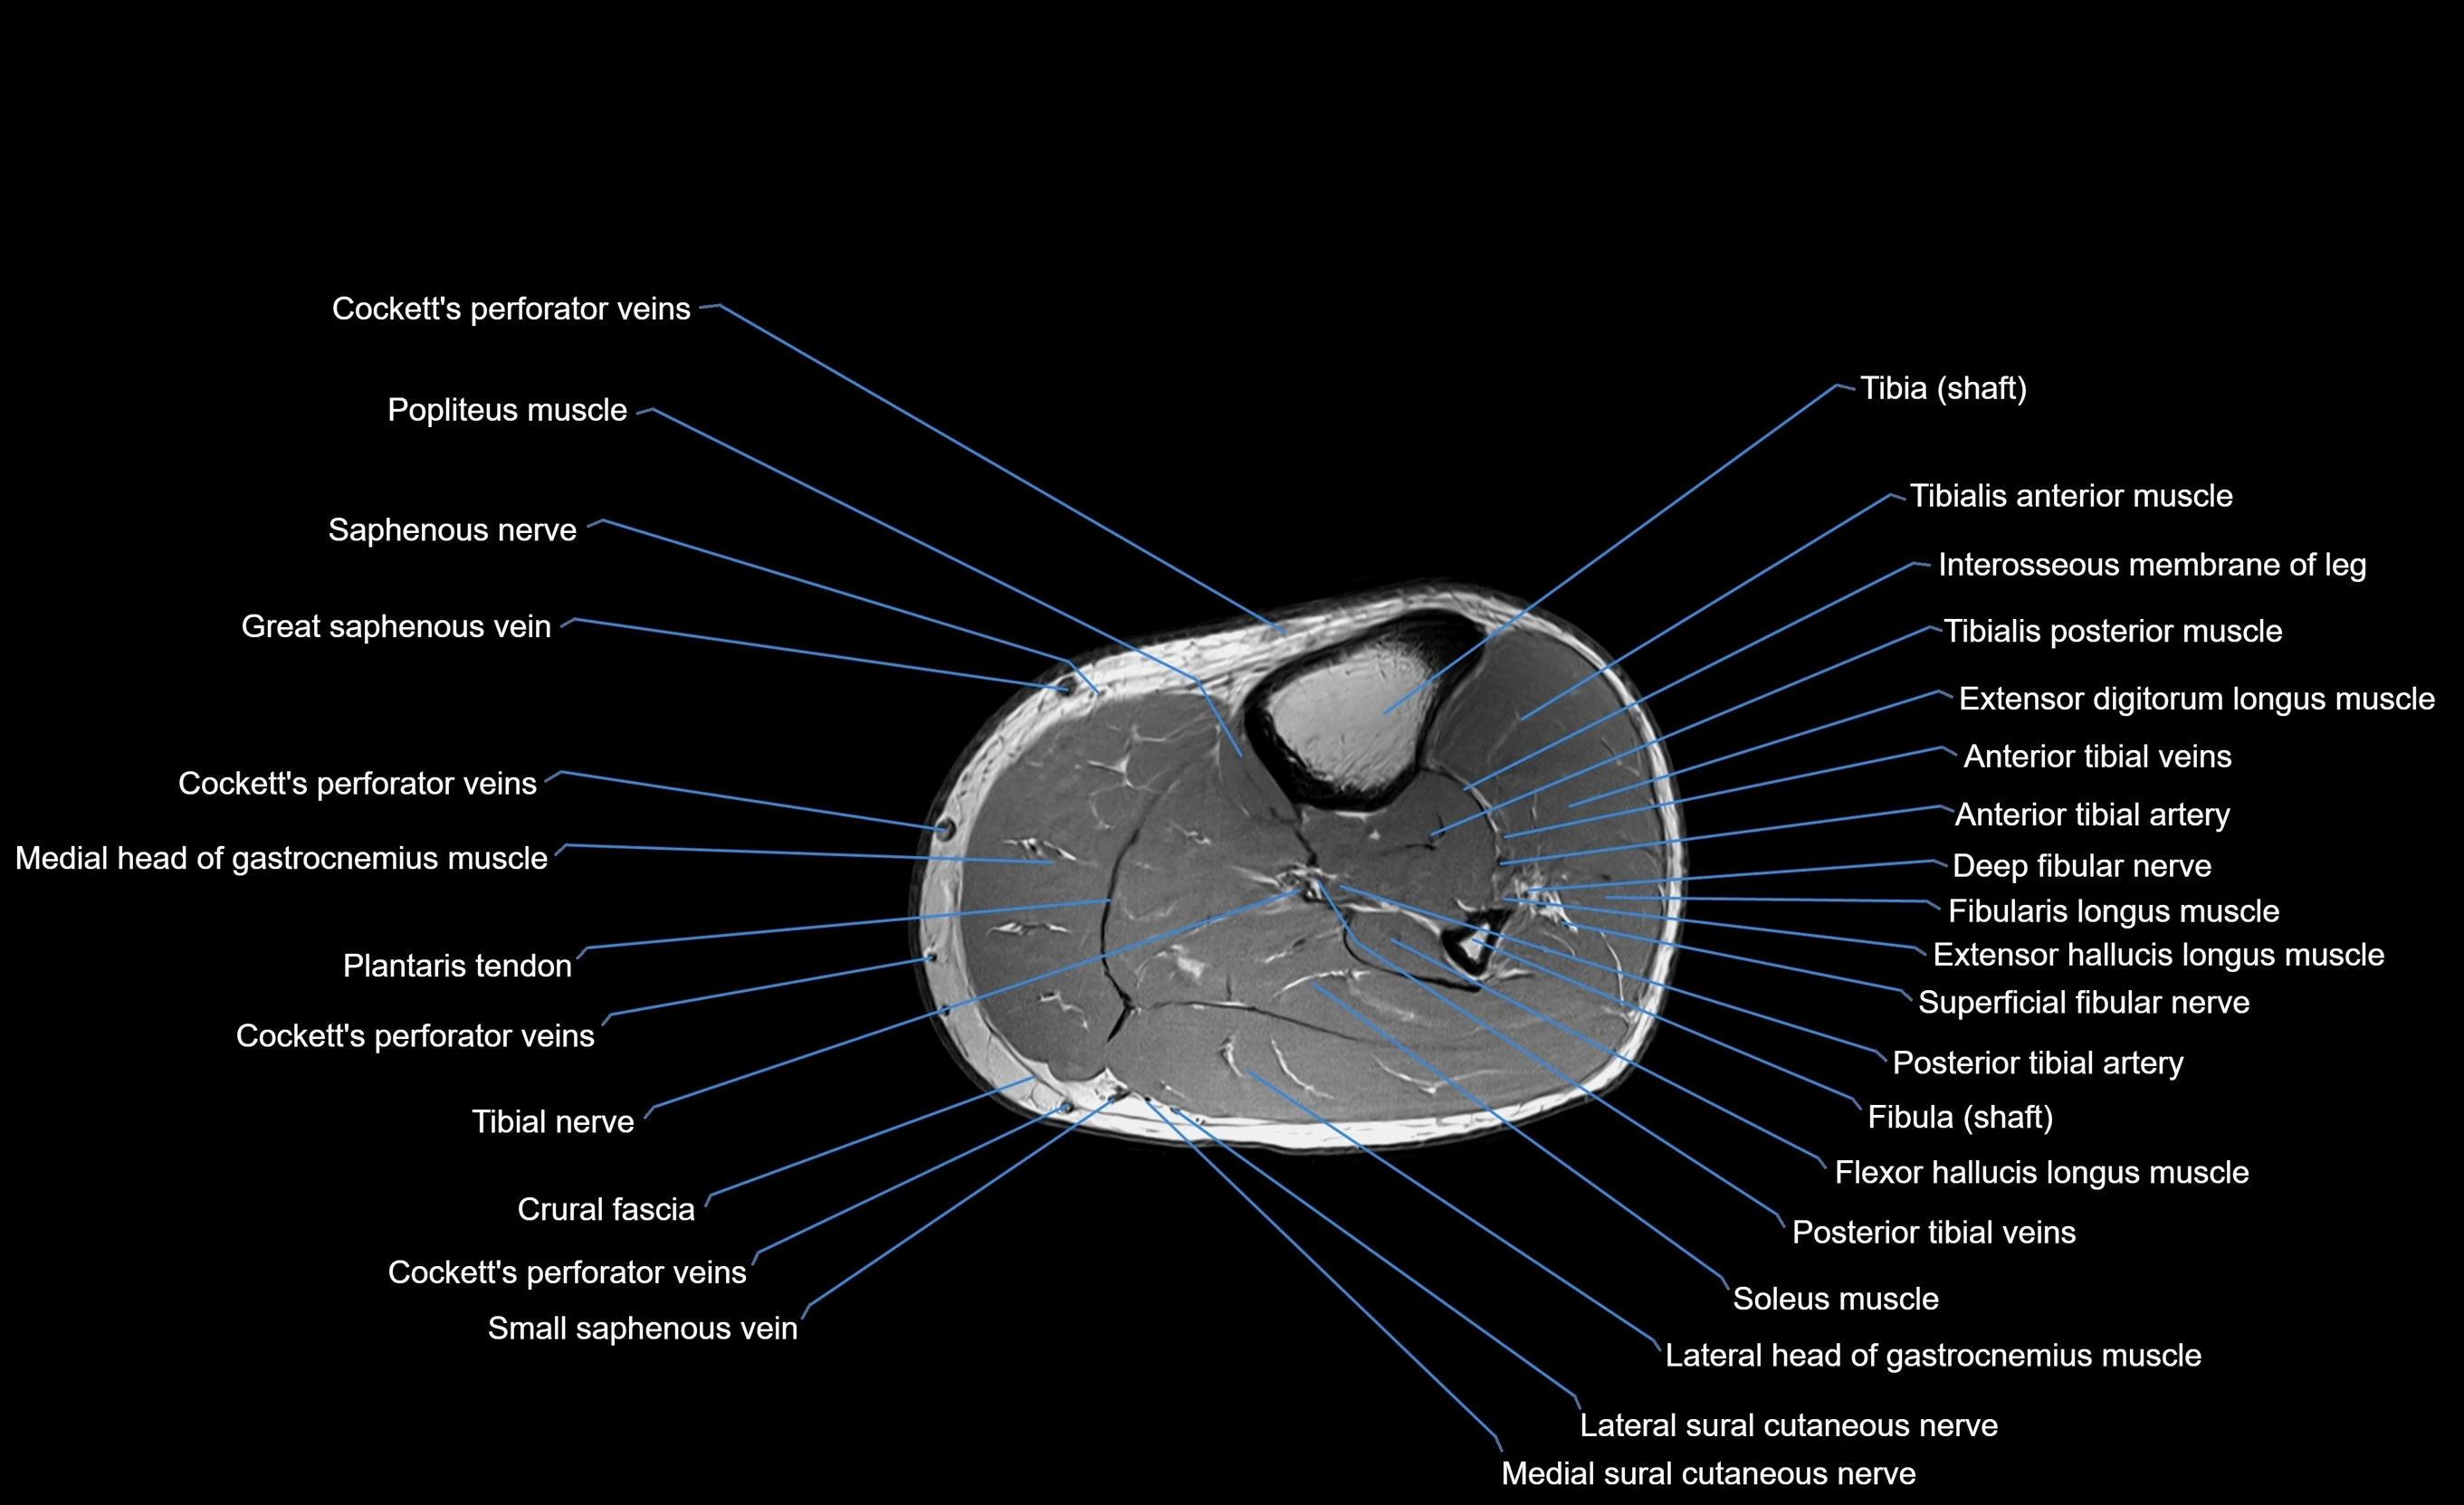

MRI image